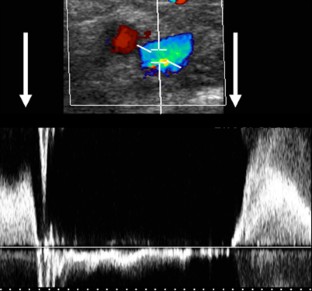

Abb. 1

Abb. 2

Abb. 3

Abb. 4

Abb. 5

Abb. 6

Abb. 7

Abb. 8

Abb. 9

Abb. 10

Abb. 11

Abb. 12

Abb. 13

Abb. 14

Abb. 15

Abb. 16